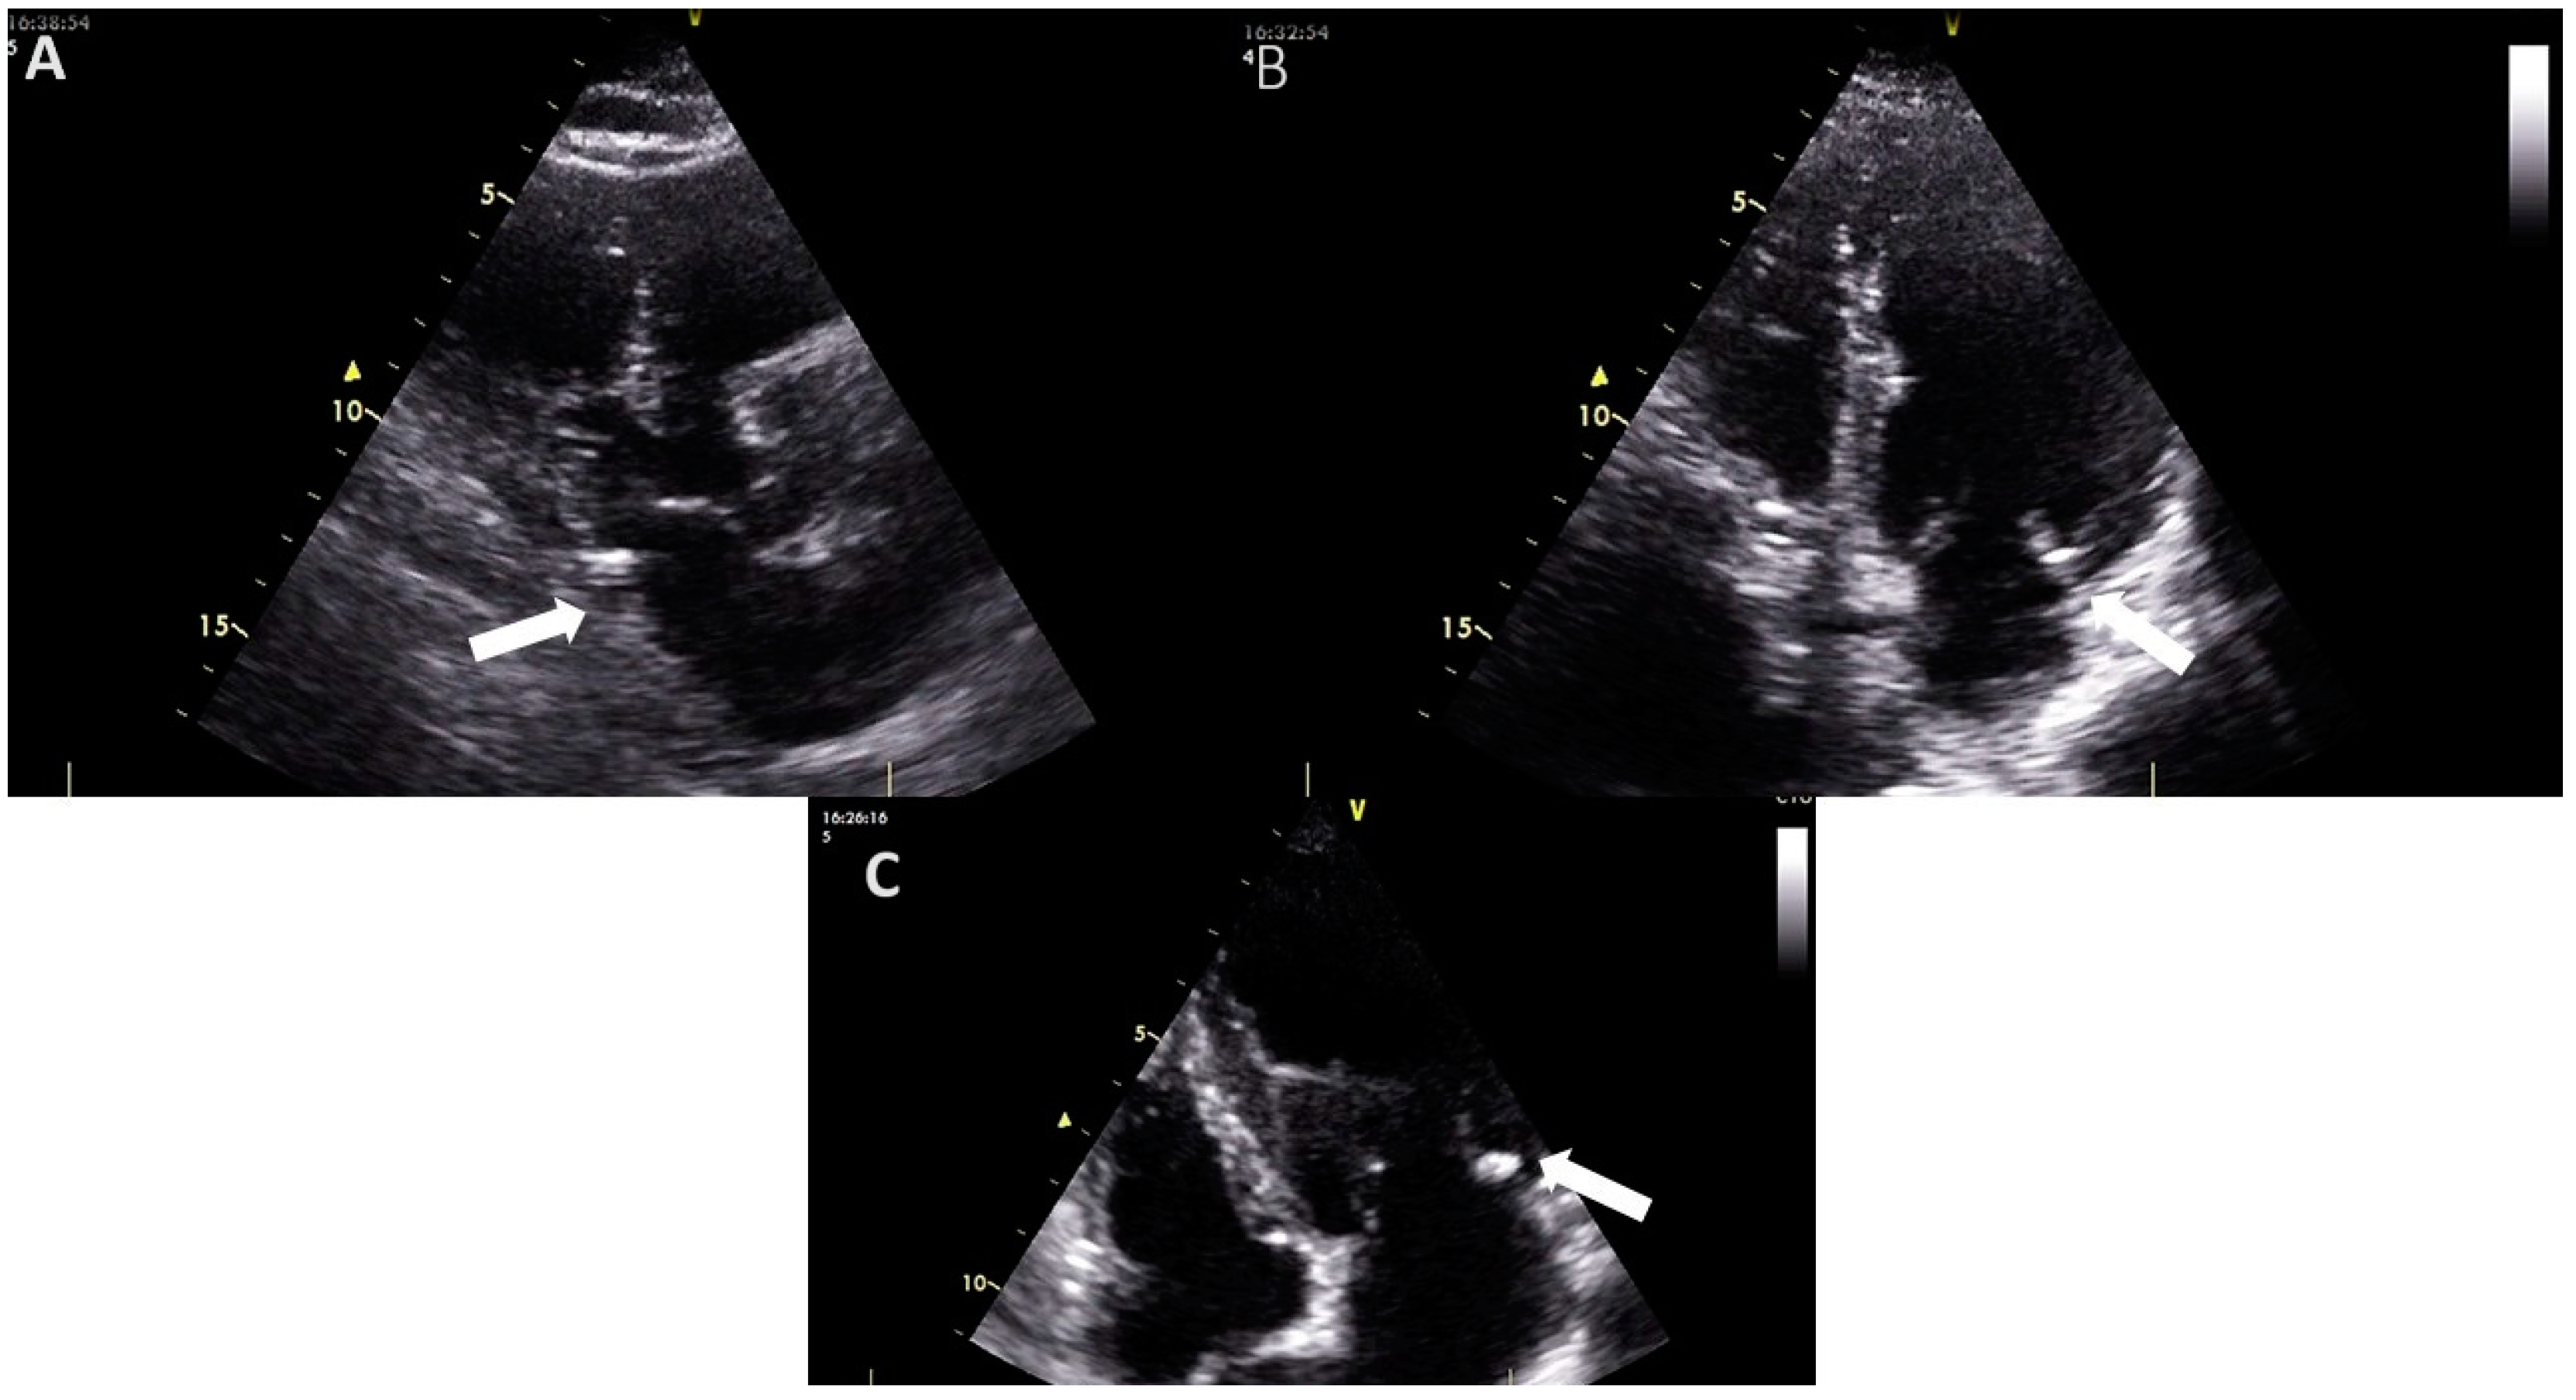

- Xu, B.; Kocyigit, D.; Wang, T.K.M.; Tan, C.D.; Rodriguez, E.R.; Pettersson, G.B.; Unai, S.; Griffin, B.P. Mitral Annular Calcification and Valvular Dysfunction: Multimodality Imaging Evaluation, Grading, and Management. Eur. Heart J. Cardiovasc. Imaging 2022, 23, e111–e122. [Google Scholar] [CrossRef]

- Harpaz, D.; Auerbach, I.; Vered, Z.; Motro, M.; Tobar, A.; Rosenblatt, S. Caseous Calcification of the Mitral Annulus: A Neglected, Unrecognized Diagnosis. J. Am. Soc. Echocardiogr. 2001, 14, 825–831. [Google Scholar] [CrossRef]

- Curl, E.; Riemer, E. Caseous Calcification of the Mitral Annulus: Case Report and Brief Review. Eur. Heart J. Case Rep. 2018, 2, yty124. [Google Scholar] [CrossRef]

- Pressman, G.S.; Rodriguez-Ziccardi, M.; Gartman, C.H.; Obasare, E.; Melendres, E.; Arguello, V.; Bhalla, V. Mitral Annular Calcification as a Possible Nidus for Endocarditis: A Descriptive Series with Bacteriological Differences Noted. J. Am. Soc. Echocardiogr. 2017, 30, 572–578. [Google Scholar] [CrossRef] [PubMed]

- Shohat-Zabarski, R.; Paz, R.; Adler, Y.; Vaturi, M.; Jortner, R.; Sagie, A. Mitral Annulus Calcification with a Mobile Component as a Possible Source of Embolism. Am. J. Geriatr. Cardiol. 2001, 10, 196–198. [Google Scholar] [CrossRef]